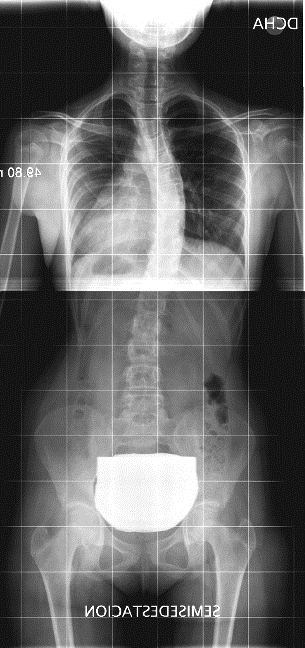

Pero, a veces ocurre que la columna no se ve perfectamente derecha4. ¿Cómo reconocer que se trata de una escoliosis posicional o actitud escoliótica? (Figura 4): los hombros deben estar a la misma altura, porque la articulación del hombro y la pseudoarticulación, escápulo-torácica, se mueven sin influir en la posición de la columna. Ascienden o descienden la clavícula con su movimiento, pero el raquis puede mantenerse perfectamente recto.

Figura 4. Posición inadecuada, actitud escoliótica. Mostrar/ocultar

Una curva larga de toda la columna vertebral dirigida hacia el hombro que se ve más caído indica que el paciente se inclinó armónicamente hacia ese lado (Figura 5). Asimismo, una curva dirigida hacia la pelvis que se eleva, o hacia el miembro que se apoya menos, posiblemente son posicionales.

Figura 5. Escoliosis posicional. Inclinación del hombro hacia el lado más bajo. La columna vertebral se curva hacia el hombro que se ve más caído, indica que el paciente se inclinó armónicamente hacia ese lado. Mostrar/ocultar

En las dismetrías, el paciente caerá hacia el lado más bajo, como mencionamos sobre la Figura 5, pero para compensar este desequilibrio la columna puede inclinarse hacia el lado más alto, bajando el hombro de ese lado. Estas curvas son lógicas y no son escoliosis. Sin embargo, podemos encontrarnos con situaciones contradictorias o mixtas (Figura 6).

Figura 6. Escoliosis posicional. Dismetría de miembros inferiores: la columna vertebral se inclina hacia el lado más alto y además eleva el hombro del mismo lado. Es una situación mecánicamente ilógica, debida a posiciones que adoptan los pacientes en el momento de hacer la radiografía. . Mostrar/ocultar